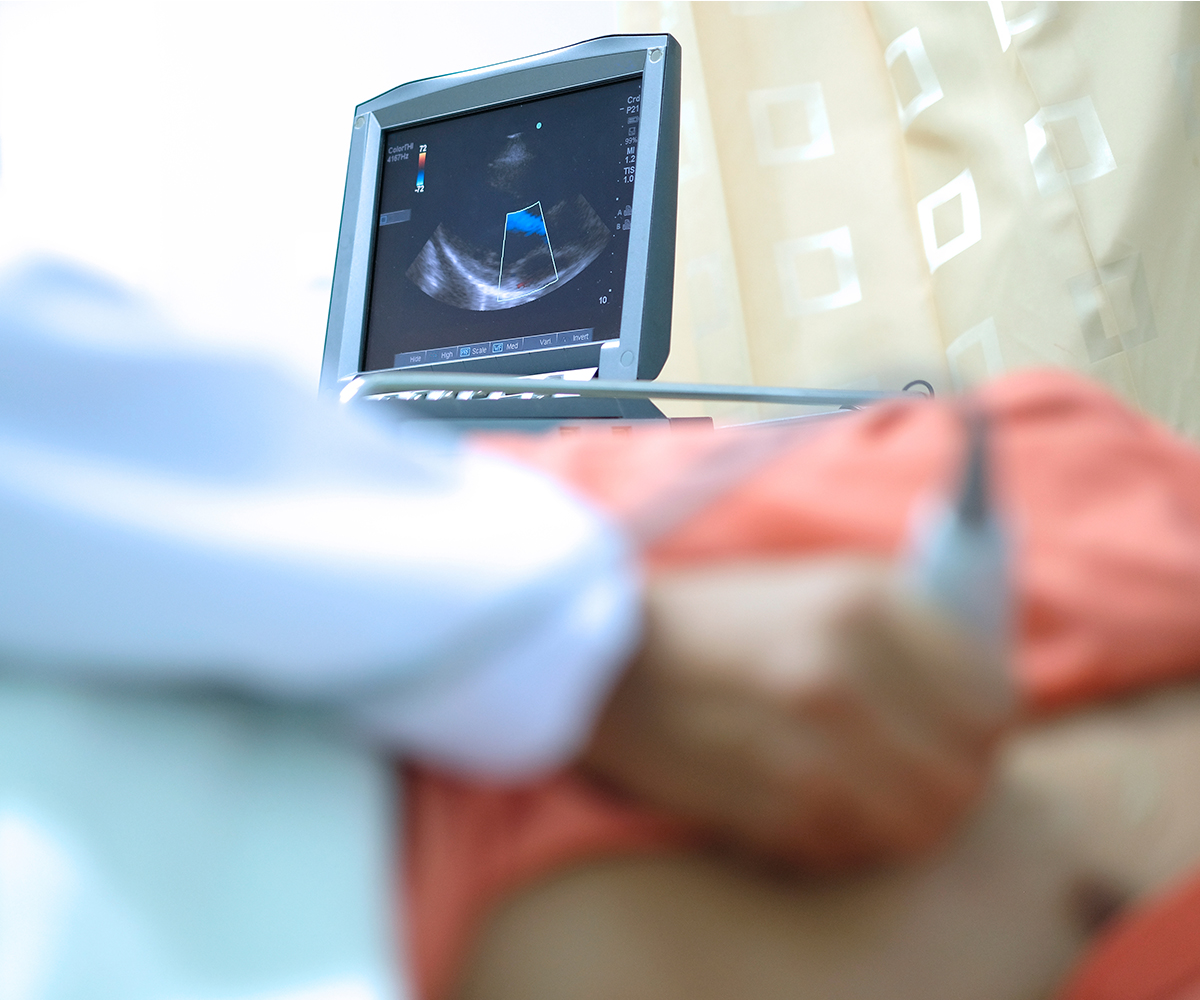

An Echo uses sound waves to create images of your heart. These visuals allow us to observe how the heart moves and pumps and to pinpoint any abnormalities.

A TTE is the most common type of echocardiogram. During the process, you will lie down on the patient bed and Dr Mgidlana will apply a special gel on your chest to help sound waves travel. The, he uses a device known as a transducer to send out sound waves and receive echoes that bounce back from the heart structures. The entire process is painless and usually takes less than an hour.